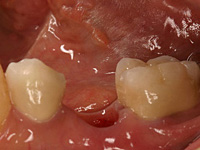

奥歯がムシ歯で抜歯になりました。

両隣の歯に負担をかけることなく、歯の治療を行いました。

1本のインプラントで1本の歯を作りました。

術前 上部構造 術後